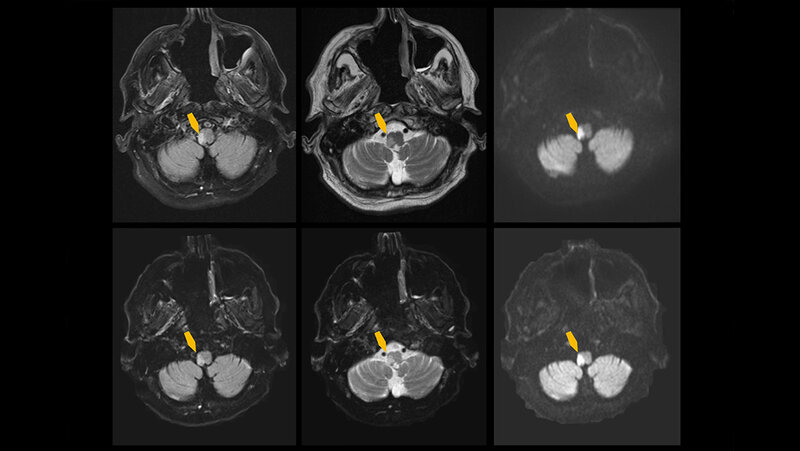

Das bisher schnellste Verfahren zur Diagnostik eines Schlaganfalls ist die CT. Doch gerade bei leichten Schlaganfällen mit schwachen neurologischen Symptomen kann ein falsch negatives Ergebnis erfolgen, da die Bildgebung nicht präzise genug ist für diesen Zweck. Während im MRT auch kleinste ischämische Infarkte erkennbar sind, führen relativ lange Aufnahmezeiten zu einem eingeschränkten Einsatz in Notfallsituationen. Das Ziel des Mainzer Forschungsteams war es, mithilfe von KI diese Untersuchungszeiten zu reduzieren.

„Die sogenannte Deep Learning-Technik ist eine noch relativ neue Technik in der medizinischen Versorgung. Die KI ermöglicht, dass MRT-Bilder parallel zur Aufnahme verarbeitet werden können und ist so trainiert, dass sie die aufgenommenen Bilder künstlich verbessern kann. Dadurch konnten wir die MRT-Bilder ultraschnell und in hoher Qualität rekonstruieren und die Zeit zwischen Untersuchungsbeginn und Befund um rund 78 Prozent reduzieren“, erläutert Dr. Sebastian Altmann, Erstautor der Publikation. In der Studie eingeschlossen waren 211 Patientinnen und Patienten mit Verdacht auf Schlaganfall, die sowohl mit der konventionellen MRT als auch der KI-gestützten MRT untersucht wurden.

Während die Untersuchungszeit der konventionellen MRT bei rund 14 Minuten lag, verkürzte sie sich beim KI-Modell auf 3 Minuten – mehr als das Vierfache weniger. Zudem zeigt die neue Methode eine bessere Bildqualität, da die Bilder mithilfe der KI verbessert wurden. Beide Methoden waren akkurat in ihrer Diagnostik und zeigten eine gute bis ausgezeichnete Zuverlässigkeit, den ischämischen Schlaganfall zu erkennen. Die KI-gestützte MRT zeigte sogar eine exzellente diagnostische Sicherheit von 96 Prozent, die konventionelle Methode lag bei 92 Prozent.